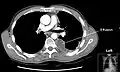

Chest computed tomography is more accurate for diagnosis and may be obtained to better characterize the presence, size, and characteristics of a pleural effusion. Lung ultrasound, nearly as accurate as CT and more accurate than chest X-ray, is increasingly being used at the point of care to diagnose pleural effusions, with the advantage that it is a safe, dynamic, and repeatable imaging modality.[18] To increase diagnostic accuracy of detection of pleural effusion sonographically, markers such as boomerang and VIP signs can be utilized.[19]

CT scan of the chest showing a left-sided pleural effusion. The fluid usually settles at the lowest space due to gravity; in this case, at the back because the patient is supine. -